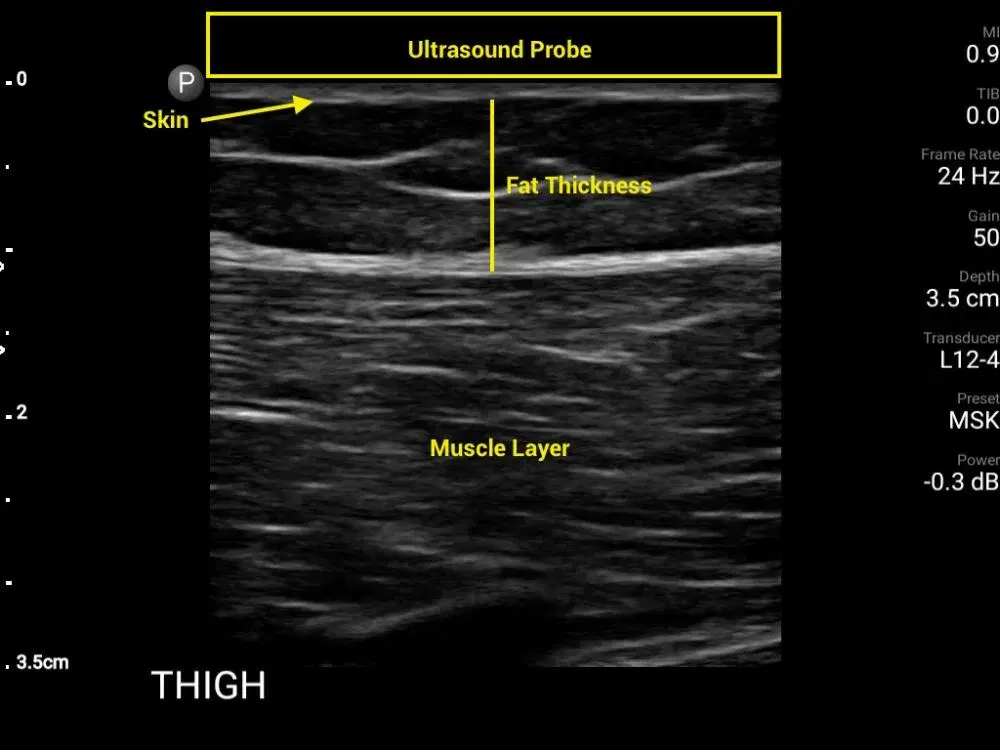

Unlike older fat freezing machines that still use tape or pinch-based estimates to measure fat, our advanced diagnostic tools minus the guesswork with the use of ultrasound at 7.5 MHz to measure with pinpoint precision. It not only helps to perform fat freezing by cooling the targeted zone to -12°C, it is also enhanced with advanced intelligence to activate the fat browning process.